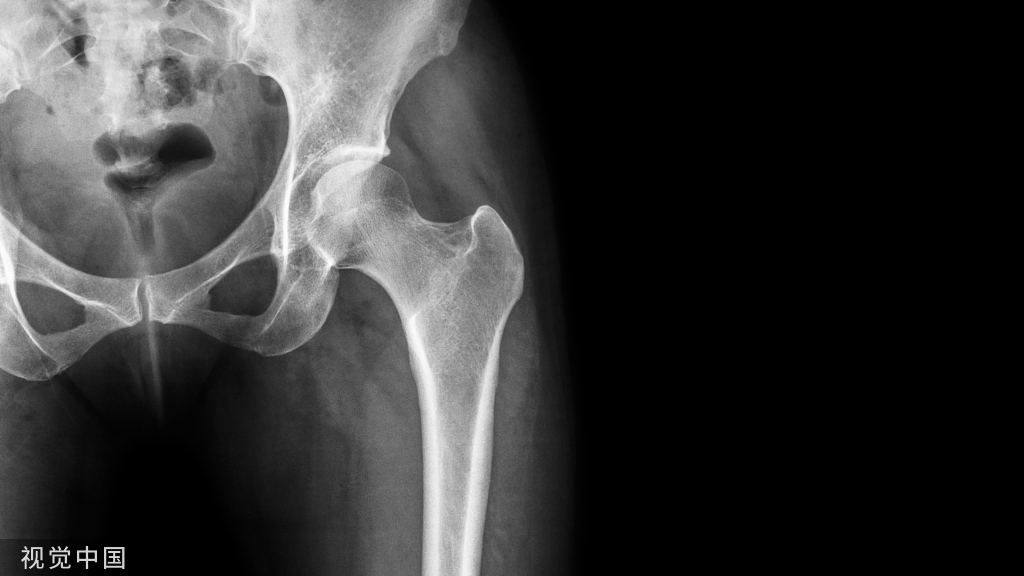

由于特殊类型骨折不属于很常见的骨折,诊断、治疗不及时往往会带来诸多更为严重的不良后遗症。今天给大家分享这40种骨折,你在临床都遇见过吗?